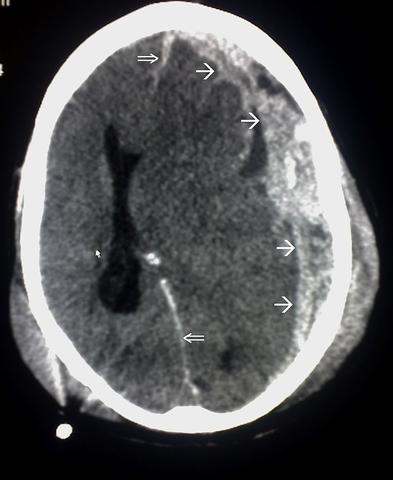

Die Diagnose eines Schädel-Hirn-Traumas wird im Krankenhaus gestellt. Neben einer Befragung des Verletzten und einer ärztlichen Untersuchung werden bildgebende Verfahren wie Röntgenuntersuchungen, Computertomographie oder Magnetresonanztomographie eingesetzt. Bei Bedarf können auch spezielle Untersuchungen wie die Aufzeichnung der Gehirnströme durchgeführt werden.

Die Diagnose wird im Krankenhaus gestellt. Eine sorgfältige ärztliche Untersuchung des Kopfes, der Hirnfunktionen und nötigenfalls des gesamten Körpers wird durchgeführt. Zusätzlich können Röntgenuntersuchungen, Computertomographien oder Magnetresonanztomographien zur Sicherung der Diagnose verwendet werden.